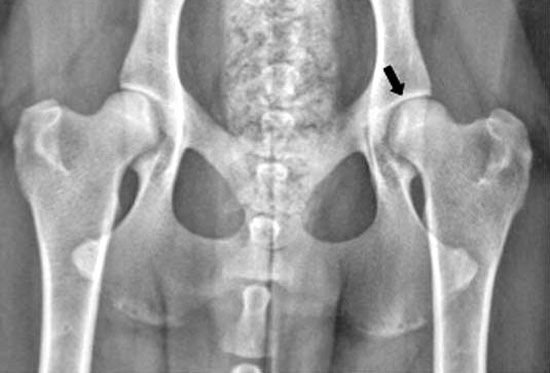

Displasia dell'anca: La radiografia (raggi X) del bacino di un cane normale. La testa del femore (freccia) è seduto profondamente all'interno dell'acetabolo, indicando congruenza eccellente dell'anca.